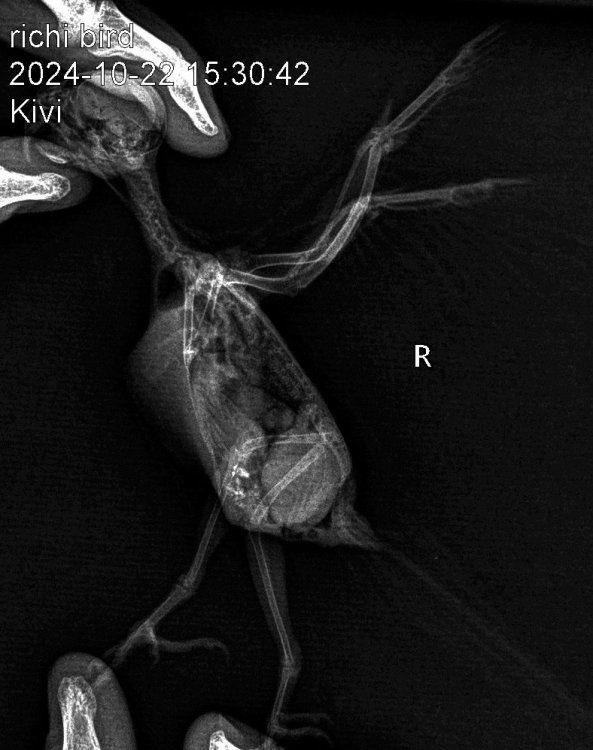

ДианаРикки Опубликовано 23 октября, 2024 #1 Опубликовано 23 октября, 2024 Вчера были на приеме у орнитолога, в Тбилиси. К сожалению, сказали очень печальный прогноз. Вес птицы всего лишь 28 грамм, критический. Сделали рентген, узи. Обнаружили кистообразную опухоль, начало подагры. Прикреплю вам файлы. И диагноз врача. Если вам не сложно, ознакомьтесь, пожалуйста. Сказали только обезбаливать анальгином. Больше никакого лечения. Даже предлагали усыпить, так как птица может испытывать боли, но рука не поднялась. Скажите, пожалуйста, насколько верен диагноз и настолько ли все плачевно или есть какие-то альтернативные варианты лечения? И можно что-то попробовать. Птица клюет шелушит зерна, но не ест. Пытаемся насильно кормить кашей. Отправили домой доживать свои дни. Не назначили никакого лечения, так как вес птицы очень мал. Также сказали не кормить насильно. Но я все де думаю, что опускать руки еще рано и может как-то можно набрать вес, чтобы провести лечение. Ведь подагру можно поддерживать , пока она не распространилась на органы. С каждым днем птице становится хуже. Прикрепляю диагноз врача и снимки рентгена. Спасибо